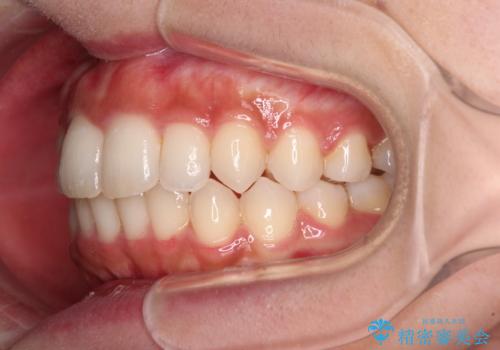

- 上下前歯のデコボコを気にして来院された患者様です。

前歯のセラミックが装着されている歯は、歯根が短くなっており、他院では抜けてしまうので矯正はできないと言われていたようです。

患者様と相談し、抜けてしまった場合にはインプラントあるいはブリッジによる補綴治療が必要となることを確認し、極力歯根に負担のかからないような仕上がりで治療を進めて行くこととしました。

デコボコを解消には、IPR(歯と歯の間を削る)をメインに歯列排列を設計し、インビザラインにて矯正治療を行うこととしました。

レントゲン写真上では、矯正治療前後で歯根長さに大きな違いはなく、抜歯を回避することができました。

上顎内側に転位している前から2番目の歯は移動が難しく、無理矢理歯根全体を動かそうと設計すると、歯肉退縮・歯髄壊死・歯根吸収といった危険性が増すため、無難なゴールにて治療を終えることとなりました。